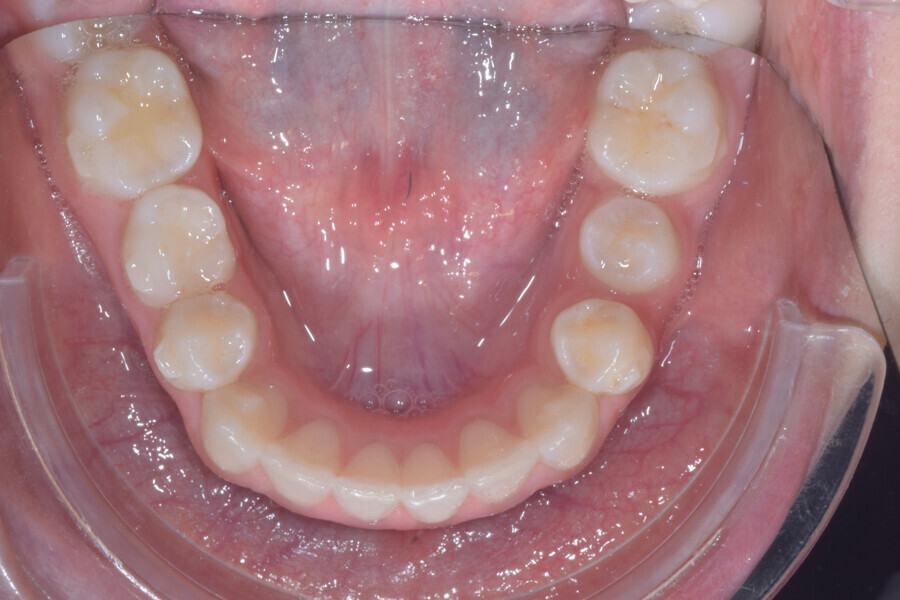

A 14-year-old female patient presented with the chief complaint of midline deviation and dental crowding in both arches. Facial analysis showed a hypodivergent growth pattern, a normal nasolabial angle, a harmonious profile and proper chin projection. Clinical examination revealed a Class III skeletal relationship (ANB = 0°) and Class I molar relationship. The maxillary right canine was absent, and this had led to space loss and mesial drift of posterior teeth on the right side, resulting in a slight Class II molar relationship. The maxillary left canine had erupted in a high position. The mandibular arch displayed crowding despite the agenesis of the right second premolar and the persistence of the primary molar (Figs. 3–11). The radiograph showed the probably premature loss of the maxillary right primary canine and consequently impacted maxillary right permanent canine, and the agenesis of the mandibular right second premolar and the mandibular right third molar (Fig. 12).

Fig. 3